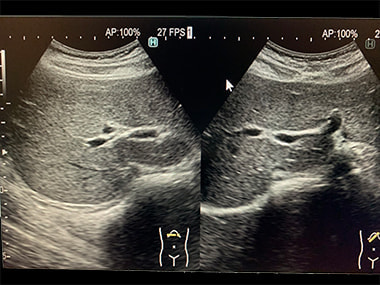

心エコー検査:

心臓が正常に働いているかどうかを調べる検査です。心臓の大きさ、動き、

弁の状態、血液の流れなどを調べ、弁膜症、心筋症、心不全などを診断します。

心臓